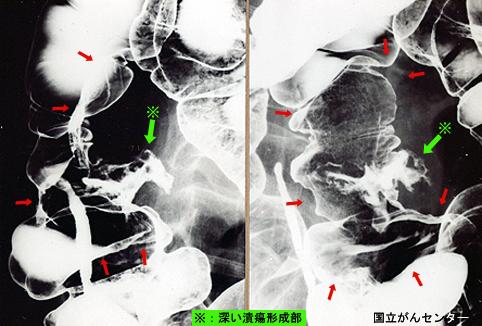

Criteria of Hist.ClassificationMalignant epithelial tumor/Undifferentiated carcinoma

LocationLarge intestine(Colon)/Ascending colon

Technique, MethodX-ray

Macroscopic TypesType 5 Unclassfied type/

Size40 -

Depth of Tumor Invasionserosa (adventitia)